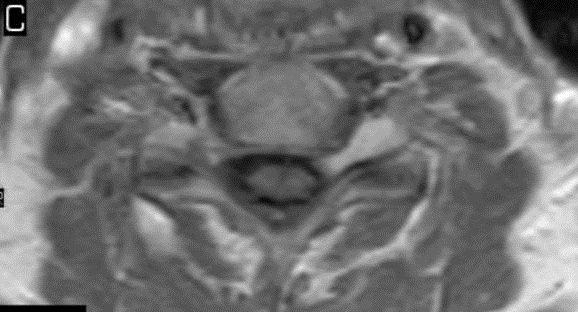

I have provided some select images from the MRI study that was obtained. Initially, the study was ordered non-contrast. Fig. 1 is a midline T-2 weighted image. It demonstrates a degree of posterior disc bulging at C6-C7. No focal posterior discal prominence was noted that would indicate a herniation. Fig. 2 is a gradient echo weighted image through the C6-C7 disc space. In this image, there is obvious expansion of the left intervertebral foramen with a degree of erosion of the facet at the posterior margin of the foramen. The signal intensity is bright on this image, compared to the normal intermediate signal intensity noted within the right foramen. You will note a degree of irregularity at the posterior margin of the disc in this cut, consistent with the disc bulging seen on the sagittal images. There is not sufficient encroachment of the central canal however to account for a neurologic deficit. A left parasagittal STIR image (Fig.3) reveals an obvious focus of abnormal signal within the left C6-C7 IVF that corresponds to the finding that was noted on the axial image. The signal intensity of this area was high on the STIR, gradient echo, and T-2 weighted images, and low on the T1 weighted images, consistent with fluid. At this point what diagnoses would you entertain, and would you order any follow-up imaging or testing?

The fluid characteristics of this lesion may be consistent with two probable considerations. It is possible that there is dilation of the dural root sleeve and that the signal represents cerebrospinal fluid. This condition is not neoplastic, but rather developmental, and does not constitute a major health concern. Another possibility is that the lesion does represent a neoplastic process. Both conditions may look similar on MRI. A rather simple way to distinguish between the two would be to perform a follow-up MRI examination with the administration of intravenous contrast (gadolinium). If the mass is neoplastic there would be expected enhancement of the mass, the signal would become brighter on the T-1 weighted postcontrast images. If the mass simply represents a fluid filled sac, such as dural root sleeve dilation or cyst, there will be no enhancement of the mass.

This patient underwent a second limited contrast examination. Pre- and post-contrast T-1 weighted images were obtained. Fig. 4 represents the pre-contrast T-1 weighted image, and Fig. 5 represents the post-contrast image at the same level. There is a quite definite increase in signal intensity of the mass on the post-contrast images. Thus, the mass is said to enhance and this is indicative of a neoplastic process. The most common extradural intraforaminal mass is a schwannoma, which represents a nerve sheathe tumor. This was the presumptive diagnosis as the patient underwent surgery for removal of the tumor. Subsequent biopsy of the lesion confirmed schwannoma. The patient did well post- surgery and the left upper extremity symptoms resolved.